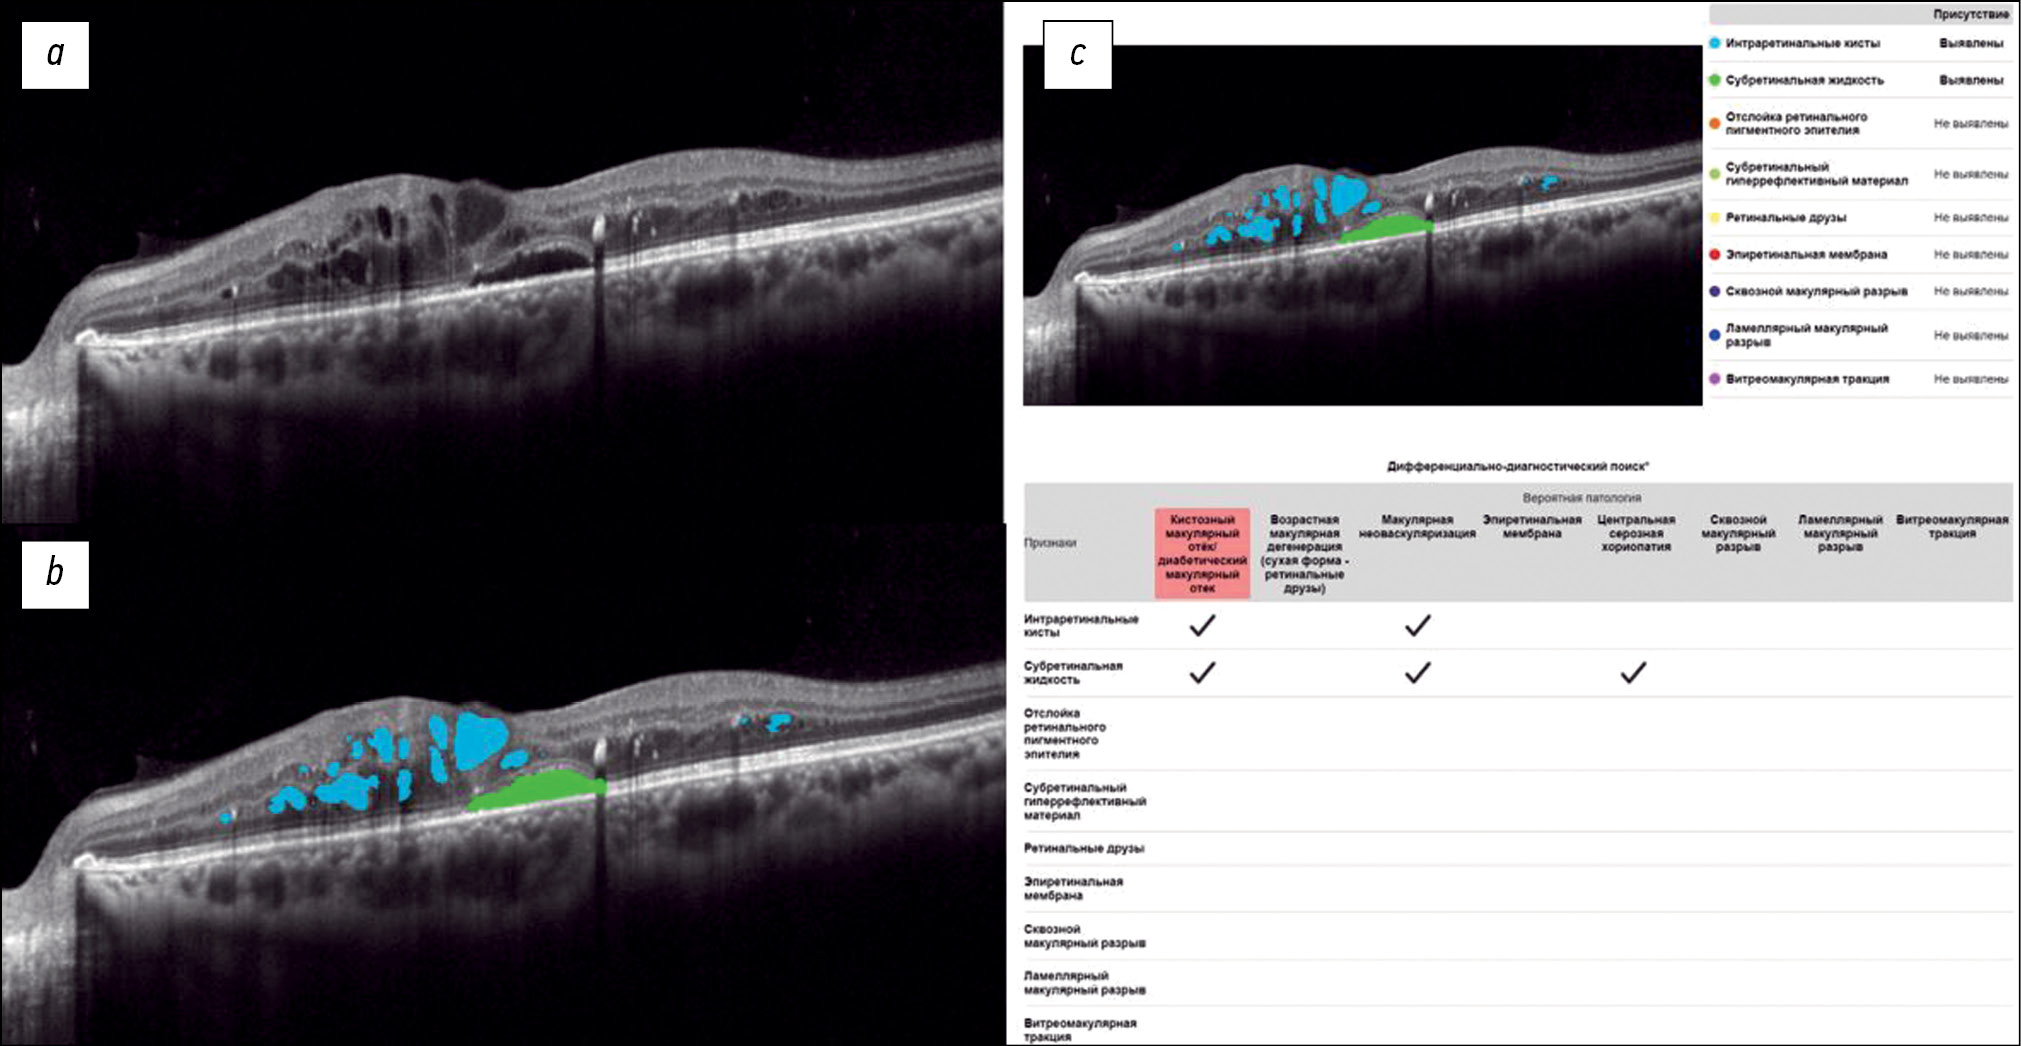

Fig. 2 shows a structural OCT scan of the macular zone of patient B (68 years old) with exudative AMD. The diagnosis was established by an ophthalmologist. In the analysis of the structural OCT scan by Retina.AI, the algorithm segmented the following pathological signs: intraretinal cysts, subretinal fluid, retinal pigment epithelium detachment, and subretinal hyper-reflective material. The program report registered macular neovascularization.

Fig. 2. An example of the optical coherence tomography scan analysis of a patient with exudative age-related macular degeneration by the artificial intelligence algorithm: a — structural optical coherence tomography scan; b — optical coherence tomography scan after segmentation of the pathological features (subretinal fluid — green mask, intraretinal cysts — blue masks, retinal pigment epithelium detachment — orange mask, subretinal hyperreflective material — yellow mask); c — scan analysis report (the reporting table of the differential diagnostic search, probable pathology is highlighted in red — macular neovascularization).